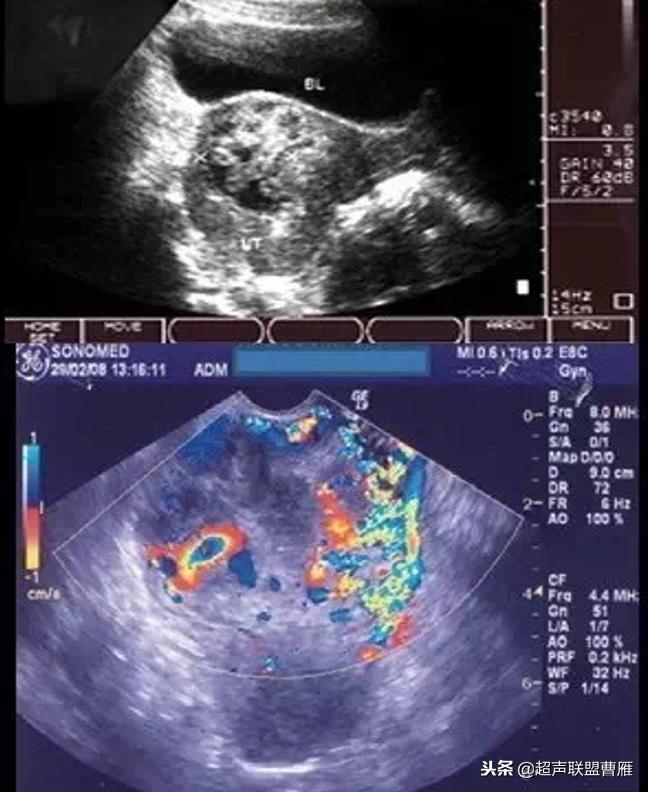

Ⅲ型类滋养细胞疾病型

1.子宫下段见梭形增大,回声杂乱不均,间有不规则液性暗区,与局部肌层分界不清

2.不均回声区内血流信号丰富,可记录到类滋养层周围血流频谱

(Ⅲ型类滋养细胞疾病型)